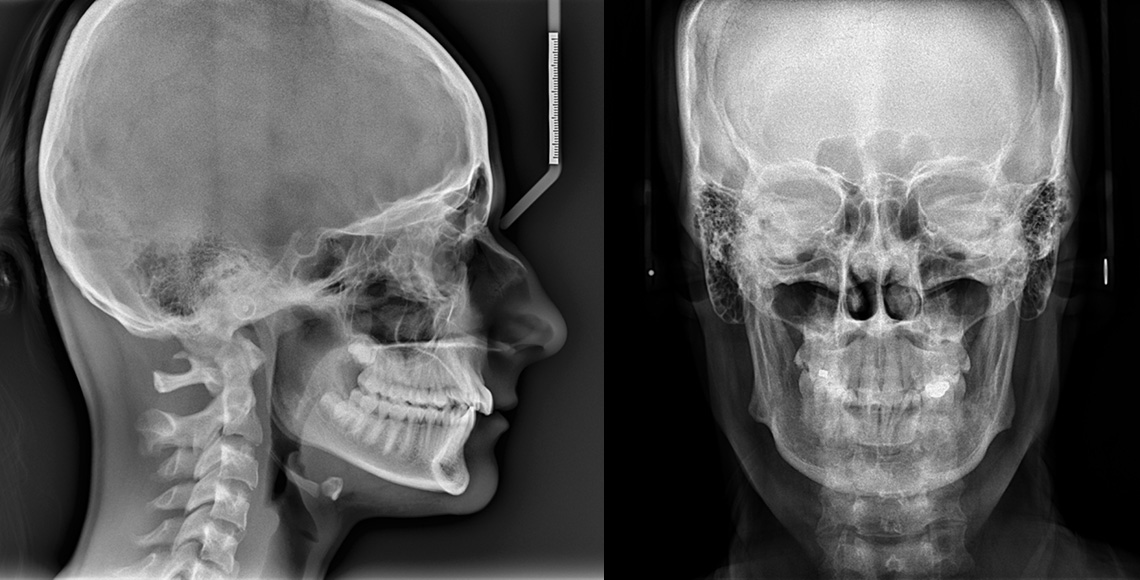

儿童正畸前后对比图

无论是口腔问题还是牙齿正畸,牙片都是检查过程中不可缺少的一环,但对于牙片你真的了解吗?